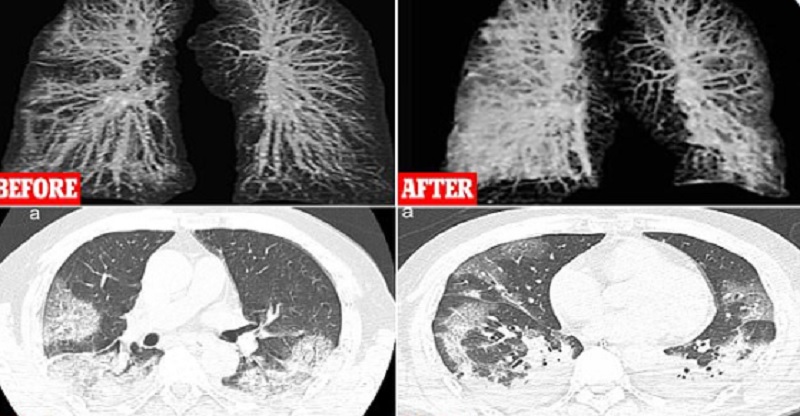

Οι ακτινογραφίες είναι από τον πνεύμονα ενός 60χρονου Κινέζου που βρέθηκε στην Ιταλία.

Στην πρώτη φωτογραφία φαίνεται ο πνεύμονας του την πρώτη μέρα που νόσησε ενώ στη δεύτερη φαίνεται όταν πλέον η κατάσταση έχει προχωρήσει.

Το ίδιο συμβαίνει και στη μαγνητική τομογραφία στους πνεύμονες όπου στη μια είναι καθαροί και στην άλλη έχουν γεμίσει πυον, νερό ή αίμα.

Τη δεύτερη σάρωση οι μαλακοί ιστοί των πνευμόνων φαίνονται εξαιρετικά διογκωμένοι.